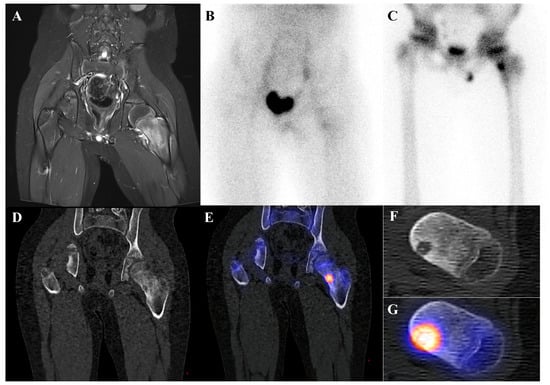

Perhaps the most critical role for [18F]FDG PET/CT in osteosarcoma management is in the evaluation of response to neoadjuvant chemotherapy. The standard of care for high-grade osteosarcoma involves preoperative chemotherapy followed by surgical resection. The degree of tumor necrosis in the resected specimen is one of the most powerful prognostic factors. A “good response,” defined as ≥90% tumor necrosis, is associated with a much better prognosis than a “poor response” (<90% necrosis). [18F]FDG PET/CT perfor-med before and after neoadjuvant chemotherapy can non-invasively predict this histologic response. A significant reduction in the tumor’s SUVmax following chemotherapy is a robust indicator of a good pathologic response [15,37,38,39,40,41,42,43]. This information can help predict prognosis and guide critical therapeutic decisions. Figure 1 demonstrates a representative case in which marked reduction of [18F]FDG uptake after chemotherapy corresponded to predominantly necrotic tissue in the resected specimen, resulting in long-term disease-free survival. This information can help predict prognosis and guide critical therapeutic decisions.

Figure 1.

A 16-year-old male with osteosarcoma of the right distal femur. (A) Pretreatment bone scintigraphy shows intense uptake in the distal femoral metaphysis. (B,C) Pretreatment [18F]FDG positron emission tomography/computed tomography demonstrates a heterogeneous, [18F]FDG-avid mass with cortical breakthrough and soft-tissue extension (SUVmax 12.6). (D,E) After neoadjuvant chemotherapy, [18F]FDG uptake markedly decreased (SUVmax 2.3) with reduction in tumor extent. (F) Wide excision specimen (×40) revealed predominantly necrotic tissue, confirming a marked response to chemotherapy, in contrast to (G) the pretreatment biopsy specimen (×100) with viable malignant cells. He has remained disease-free for 8 years.